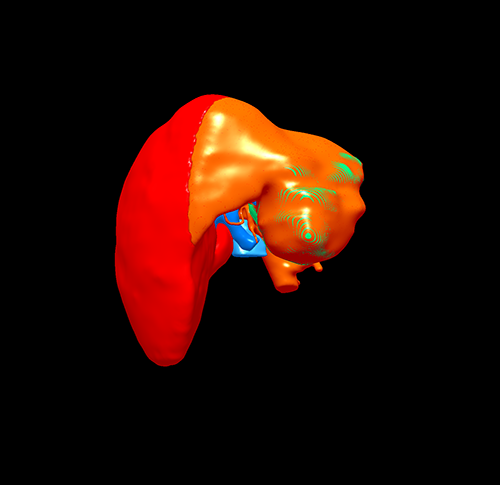

左肝癌、门静脉癌栓---左半肝切除